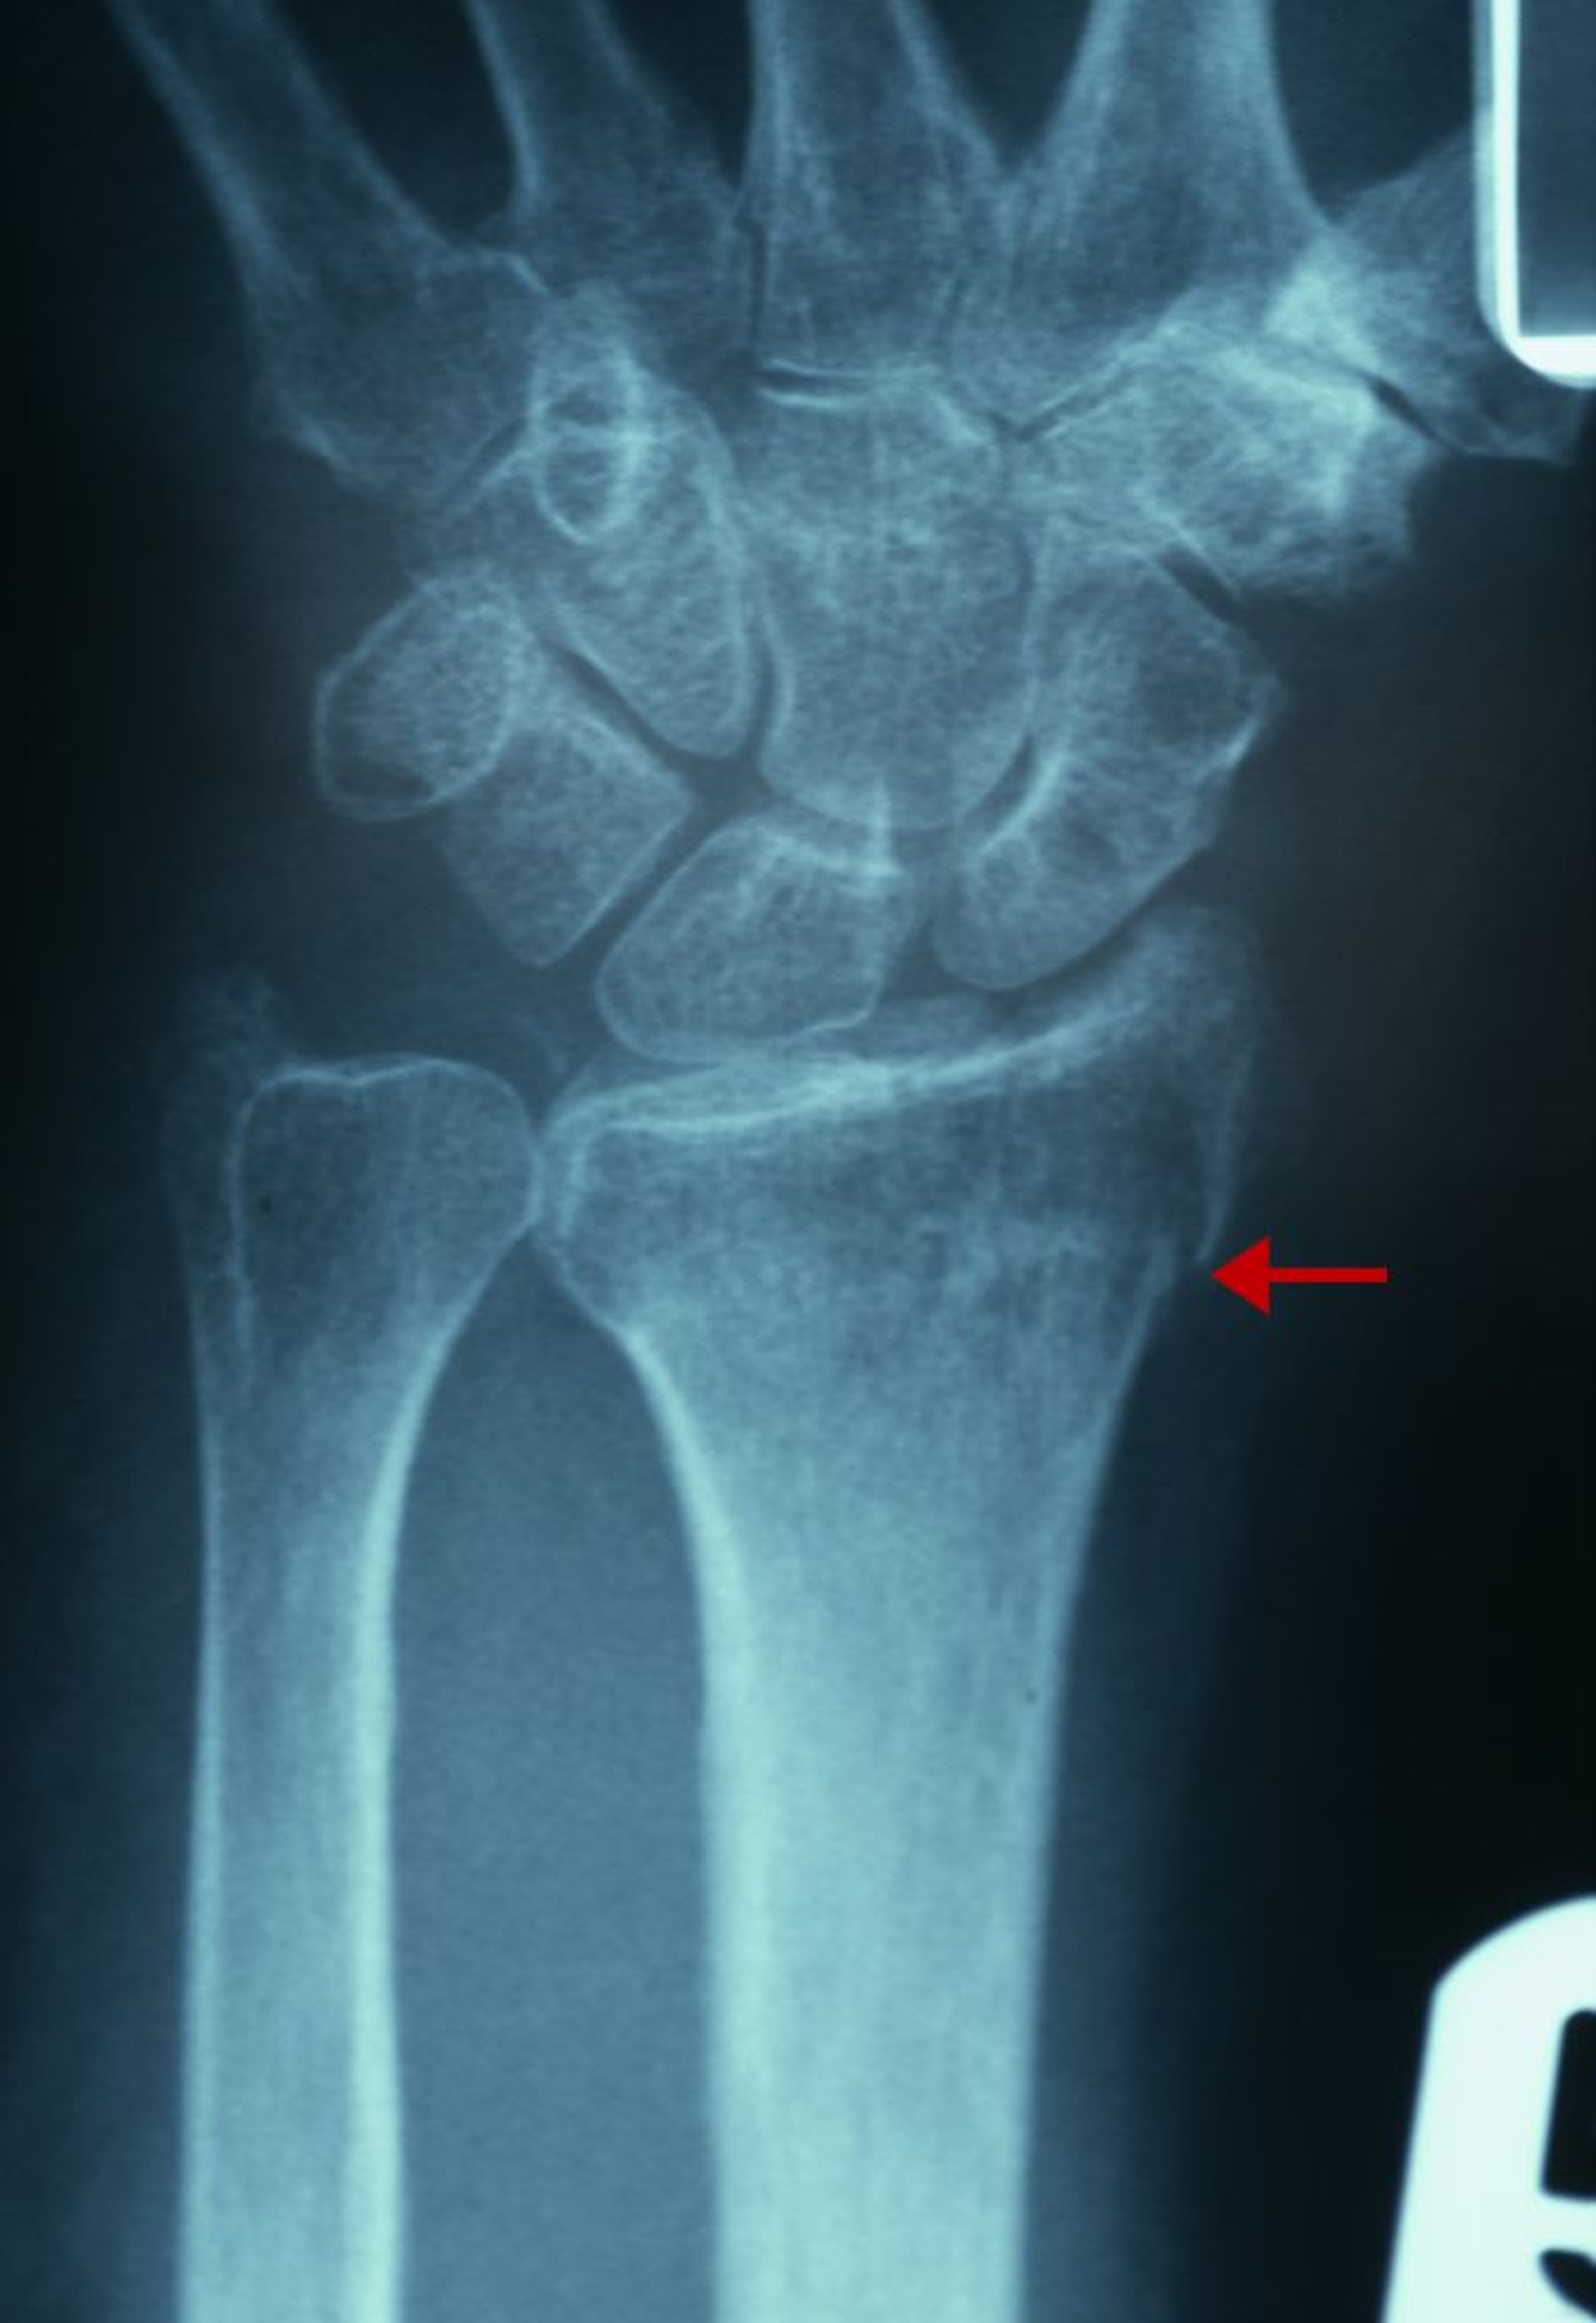

Leichte distale Radiusfraktur

Der Röntgenbefund dieser Fraktur umfasst einen Bruch der Kontinuität der Kortikalis des radialen Aspekts des distalen Radius (Pfeil) und eine Zunahme der Trabekeldichte des distalen Radius.